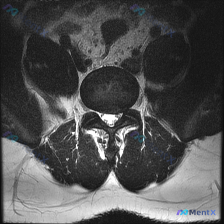

今天整理了一份只有单张腰椎MRI T2加权轴位片的椎间盘病变分析案例,跟大家分享一下读片和临床分析的思路。 病例影像基本信息 本次仅提供单张腰椎MRI T2加权轴位图像,具体读片发现如下: 1. 节段定位:根据椎体、椎弓根和关节突形态判断,该切面位于腰椎,最可能为L4/5或L5/S1水平 2. 椎间...

看到这一份腰椎MRI读片病例,临床怀疑存在椎间盘病变,我们整理一下影像资料和完整分析思路,大家一起讨论。 病例影像资料 本次提供的是腰椎MRI T2序列轴位图像,分析如下: 1. 扫描层面:位于下腰椎节段,可清晰辨认中央的硬膜囊、马尾神经根,以及侧方的关节突关节、椎旁肌肉 2. 核心影像发现: -...

这是一份单张腰椎MRI T2轴位影像的分析病例,核心问题是:临床怀疑椎间盘病变,影像上能看到什么问题?整理了完整的读片和分析思路分享给大家。 一、影像基本信息 本次提供的是腰椎MRI T2序列轴位单一层面图像,定位为腰椎椎间盘层面,我们按结构逐一读片: 1. 骨性结构与韧带:椎体形态、骨皮质连续,无...